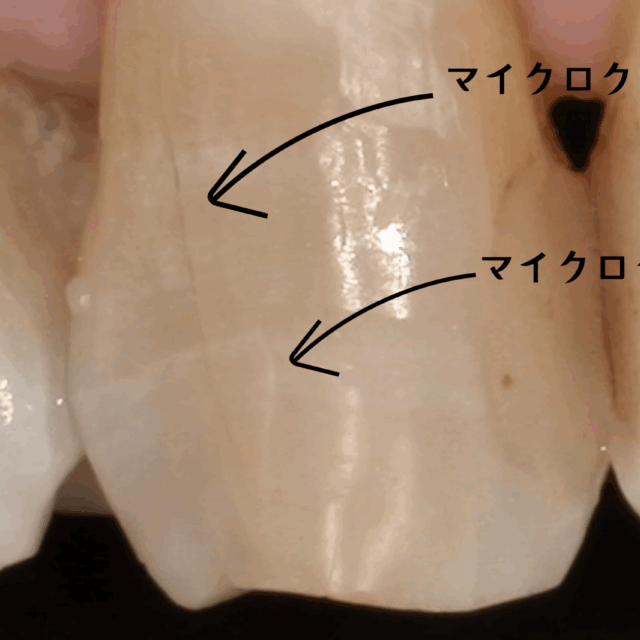

こんにちは、NK dental TOKYOの院長 堀です!今日は最近話題の「ラミネートベニア治療」についてお話しします。ラミネートベニアは、歯の表面に薄いセラミックを貼り付けることで、形や色を整え、理想的な笑顔を手に入れることができる治療法です。歯を削る量も最小限で済むため、人気が高まっています。

ホワイトニングは、歯を削ることなく自然な白さを引き出す方法です。これを先に行うことで、歯全体の色味を明るく統一し、その後に必要な部分だけラミネートベニアを施すことで、より自然で美しい仕上がりになります。

例えば、前歯の数本をラミネートベニアで整えたい場合、周囲の歯の色が暗めだとベニアを装着した歯だけが浮いて見えることがあります。しかし、先にホワイトニングを行うことで、周囲の歯と調和しやすくなり、ベニアの色選びもより自由になります。